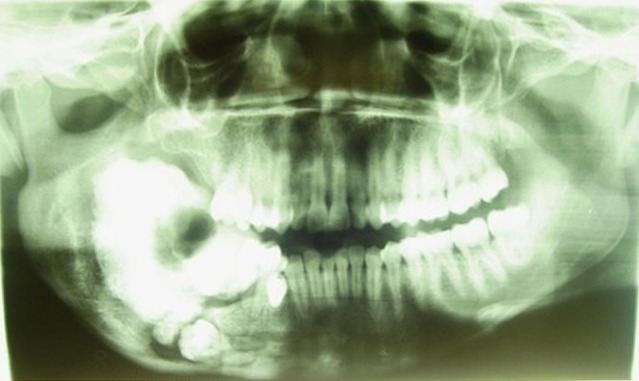

The panoramic radiographours revealed a large irregular radiopaque mass extending anteriorly from the 46 to just below the sigmoid notch posteriorly, inferiorly to just above the lower border of the mandible and superiorly to beyond the alveolar crest. The lesion was surrounded by a distinct radiolucent rim. An impacted molar tooth was located just above the lower border in line with the 46 region (Fig. 3). Further history taking revealed that this patient had previously attended our department in 2004 for the same complaint, but subsequently defaulted. She was lost to follow up until her return in 2008. The panoramic radiograph taken in 2004 showed a large radiopacity extending from the distal aspect of the 46 to the mid-ramus posteriorly and the lower border of the mandible inferiorly. There was an impacted molar at the lower border of the mandible. The lesion was surrounded by a radiolucent border, which seemed to be more pronounced in the ramus (Fig. 4). A comparison of the panoramic radiograph taken in 2004 and 2008 clearly illustrates the changes in the lesion over a 4 year period as it sequestrated into the oral cavity. In 2004 the lesion appeared to be less dense, smaller and positioned below the occlusal plane. The radiolucent rim was also narrowed. In 2008 the lesion appeared to have grown in size. It was more dense, probably an indication of its advanced stage of maturity. It had also moved to beyond the occlusal plane. The radiolucent rim was wider, and the impacted tooth seemed to have moved occlusally with an enlarged follicle surrounding its crown. The inferior alveolar canal was displaced inferiorly towards the lower border of the mandible. The radiographs of 2004 and 2008 did not show root resorption.

Fig. 3.

Pre-operative panoramic radiograph 2008; the lesion has grown since 2004 and shows clearly a well-defined radiolucent rim which is the result of overlying infection